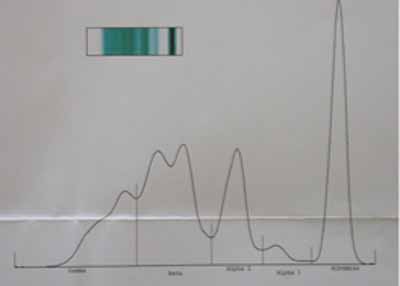

- Immunoélectrophorèse (Photo 7) : en vert les valeurs anormales

- Pt 77 g/l A/G 0.36 (Valeurs usuelles VU 60-80) (VU 0,5-1,2)

- Alb 23.3% 20.3 g/l (VU 25-35)

- Alpha 1 2.8% 2.2 g/l ((VU 5-8)

- Alpha 2 17.2 % 13.2 g/l (VU 5-10)

- Beta 36.3 % 27.9 g/l ((VU 7-12)

- Gamma 17..4% 13. 4 g/l ((VU 5-15)

Photo 7 : Immunoélectrophorèse des protéines sériques

©Photo Dr Jacques Lamothe.